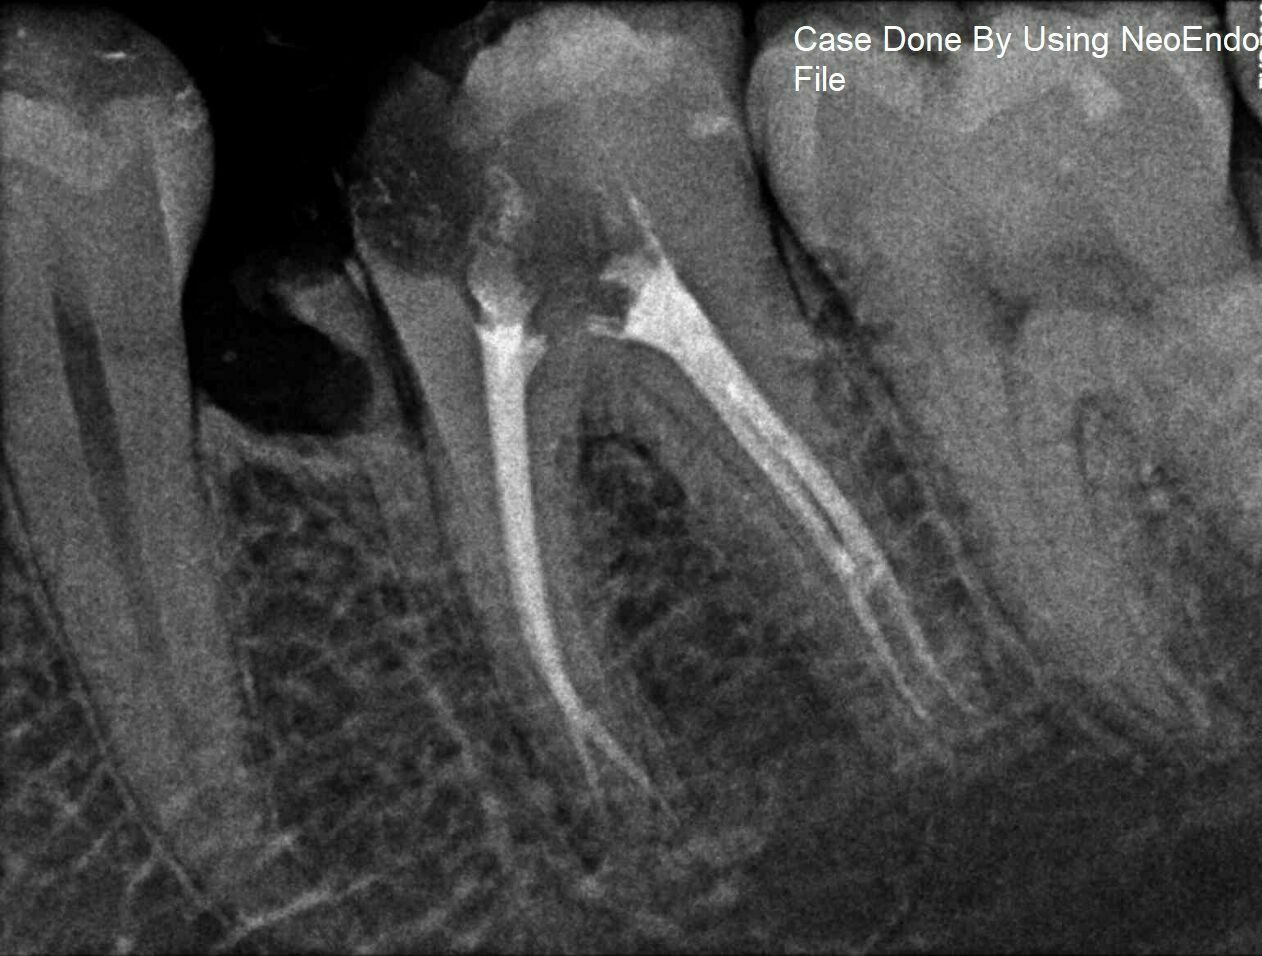

Neoendo Flex Files 21mm 6 30 Cross Section Triangular Rust Free Endodontic Files Cross Section The most commonly used type for canal root procedures. 4.1.4.3.3 k3 niti rotary endo file system (sybron endo/kerr) this system was introduced in 2002 (figure 4.14). Over time, they have varied from square to triangular and rhomboidal in. The mass of a file is defined by its geometric shape when sectioned perpendicular to its longitudinal axis. 1 2 3 characteristics. Endodontic Files Cross Section.